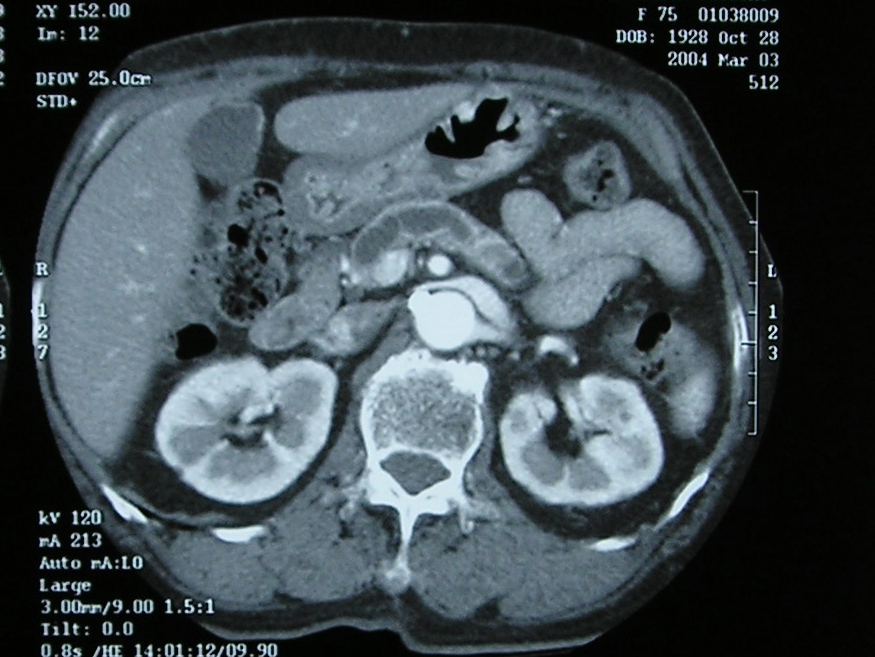

自己免疫性膵炎

体重減少、黄疸を来たした。

MRCP、膵液細胞診、超音波内視鏡を経て

血液データより最終的に診断された。

現在ステロイド服用中。

経過 良好。

膵頭部に腫瘍をみとめる。